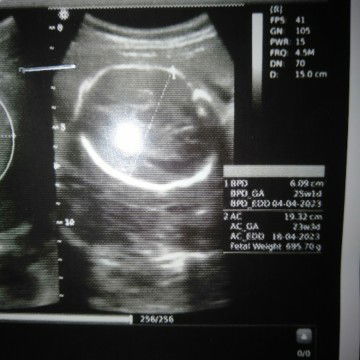

baca hasil usg

bun itu hasil usg aku kmarin itu baca hasilnya gimna ya#bantusharing